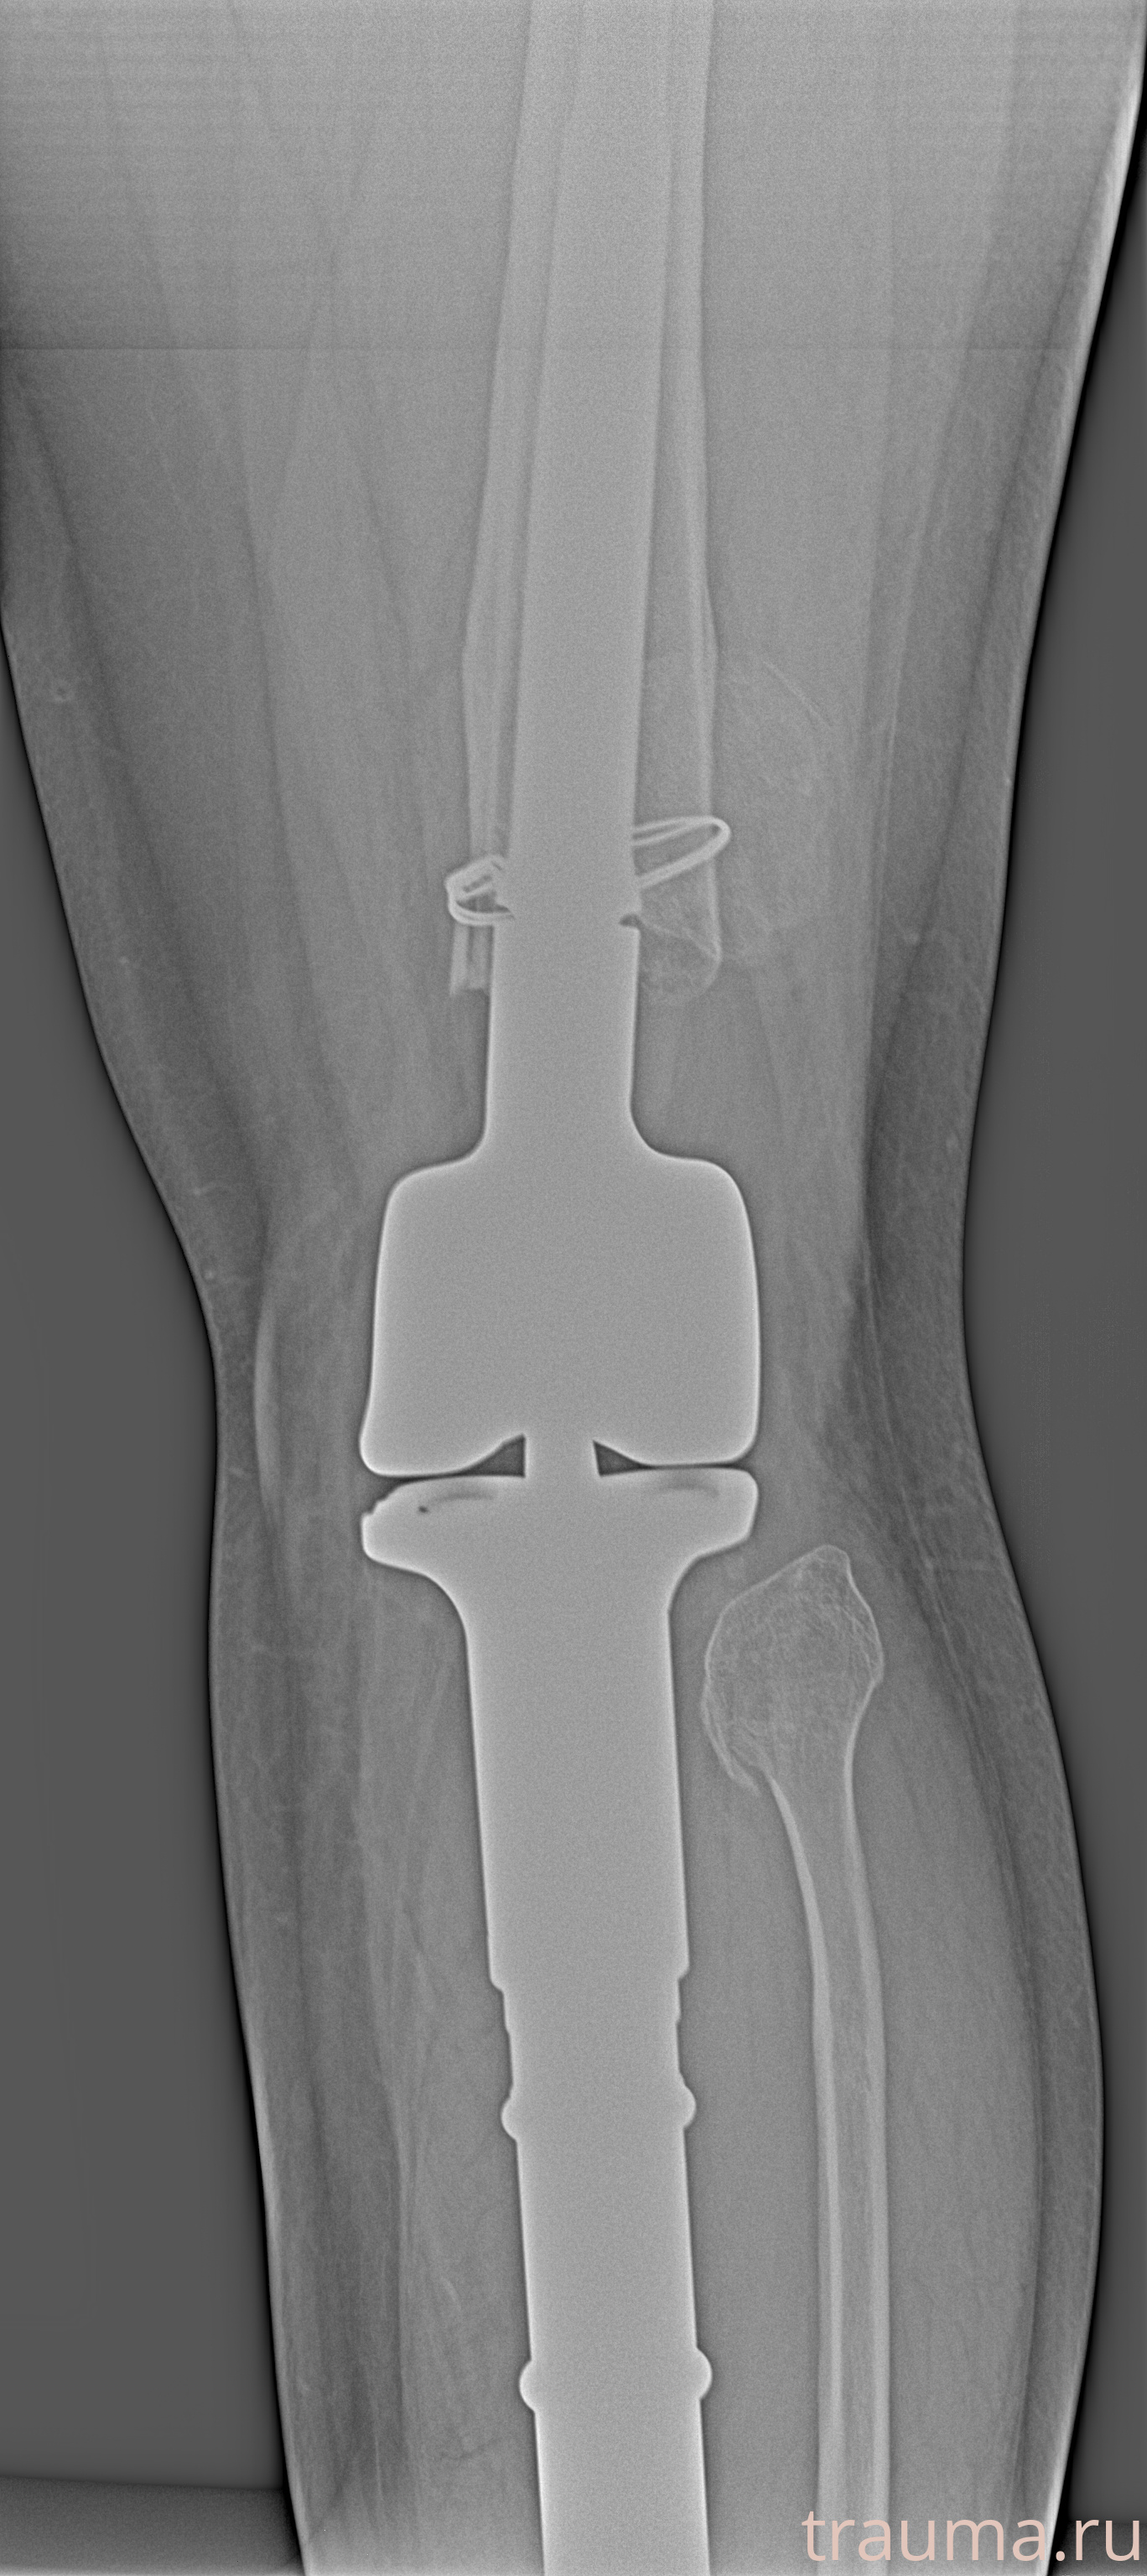

Рентгенограммы

Рентген на дому: по вашему адресу приезжает врач-рентгенолог, травматолог-ортопед с мобильным рентгеновским аппаратом, проводит диагностику травмы или заболевания, делает необходимые рентгенограммы, дает рекомендации по дальнейшему лечению. Получить качественные снимки в домашних условиях возможно благодаря уникальной методике, разработанной МосРентген Центром для института  Склифосовского